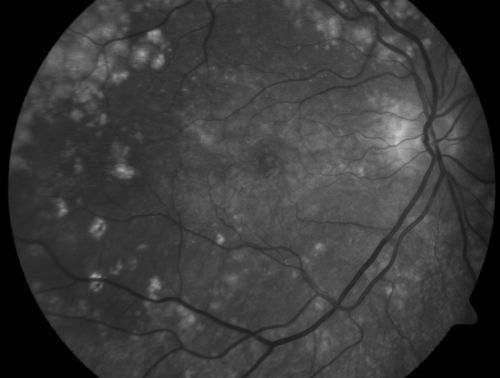

Basal Laminar Drusen - Cuticular Drusen - Equatorial Drusen - 70 Year Old Woman

70 year old woman has had macular drusen since her thirties and she said her sister has a similar problem.  Recently the vision in the left eye has substantially declined. OD 20/16, OS 10/200.